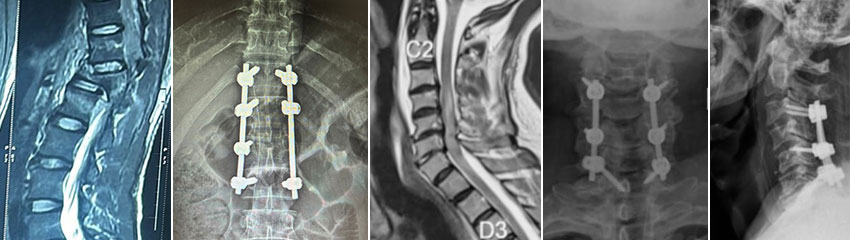

Cervical & Lumbar Disc Prolapse

A disc prolapse (commonly referred to as a herniated disc or slipped disc) occurs when the soft center of a spinal disc pushes through a tear in the outer layer, compressing nearby nerves. This can happen in both the cervical (neck) and lumbar (lower back) regions.

Cervical Myelopathy

Cervical Myelopathy is a serious condition caused by the compression of the spinal cord in the cervical spine (neck). It typically results from degenerative changes such as disc herniation, bone spurs, or spinal stenosis and leads to progressive loss of function over time.

Lumbar Canal Stenosis

Lumbar Canal Stenosis is a narrowing of the spinal canal in the lower back, leading to compression of the spinal cord or nerve roots. It is often caused by degenerative changes such as arthritis, disc degeneration, or the thickening of ligaments.